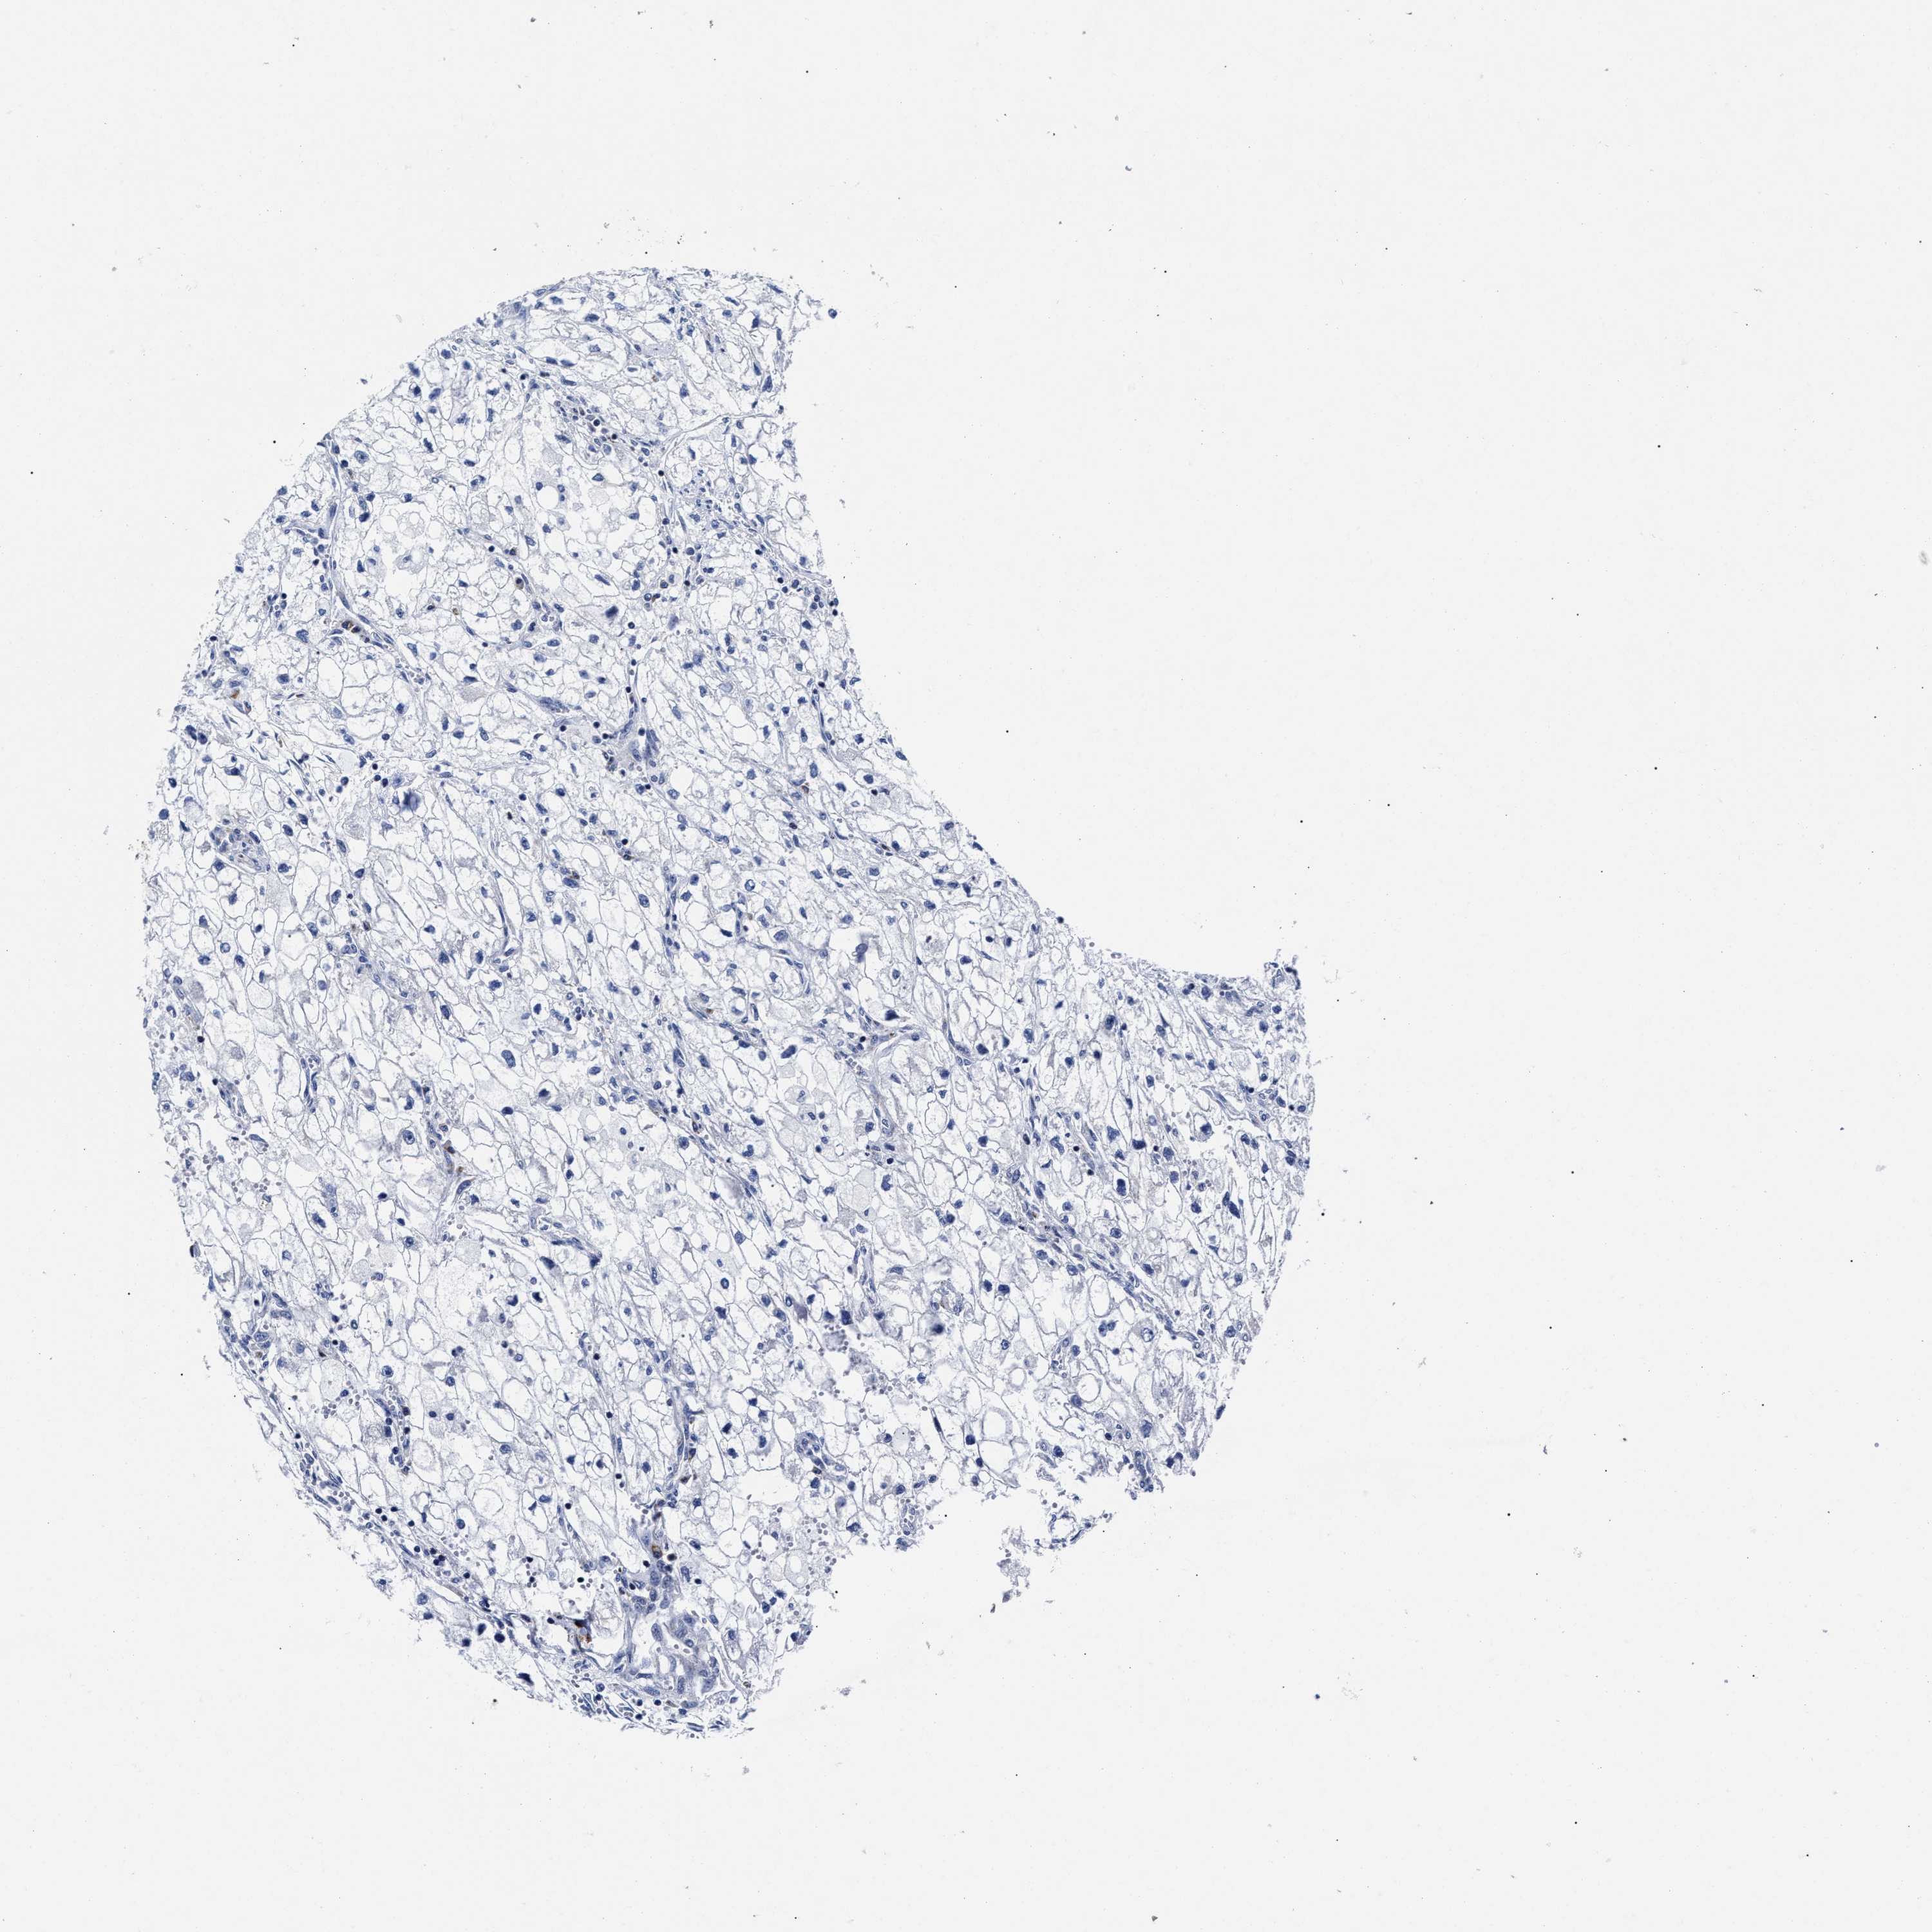

KIDNEY RENAL CLEAR CELL CARCINOMA (VALIDATION) - Interactive survival scatter ploti

The Survival Scatter plot shows the clinical status (i.e. dead or alive) for all individuals in the patient cohort, based on the same data that underlies the corresponding Kaplan-Meier plots. Patients that are alive at last time for follow-up are shown in blue and patients who have died during the study are shown in red.

The x-axis shows the expression levels (FPKM) of the investigated gene in the tumor tissue at the time of diagnosis. The y-axis shows the follow-up time after diagnosis (years). Both axes are complimented with kernel density curves demonstrating the data density over the axes. The top density plot shows the expression levels (FPKM) distribution among dead (red) and alive patients (blue). The right density plot shows the data density of the survived years of dead patients with high and low expression levels respectively, stratified using the cutoff indicated by the vertical dashed line through the Survival Scatter plot. This cutoff is automatically defined based on the FPKM cutoff that minimizes the p-score. The cutoff can be changed by dragging the vertical line or by entering a cutoff value in the square labeled "Current cut-off".

Under the Survival Scatter plot the p-score landscape (black curve; left axis) is shown together with dead median separation (red curve; right axis). Dead median separation is the difference in median mRNA expression between patients who have died with high and low expression, respectively. It is calculated as follows: median FPKM expression of dead patients with high expression - median FPKM expression of dead patients with low expression. This is intended to aid the user in visually exploring custom cutoffs and the associated p-scores and dead median separation.

Individual patient data is displayed and can be filtered by clicking on one or more of the category buttons on the top of the page. Categories describing expression level and patient information include: high, low, alive, dead, female, male and tumor stages. The scale of the x-axis can be toggled between linear and log-scale by clicking on the "x log" button. Mouse-over function shows TCGA ID, patient information and mRNA expression (FPKM) for each patient.

& Survival analysisi

Kaplan-Meier plots summarize results from analysis of correlation between mRNA expression level and patient survival. Patients were divided based on level of expression into one of the two groups "low" (under cut off) or "high" (over cut off). X-axis shows time for survival (years) and y-axis shows the probability of survival, where 1.0 corresponds to 100 percent.

HINT2 is not prognostic in Kidney Renal Clear Cell Carcinoma (validation)

Best expression cut offi

Based on the FPKM value of each gene, patients were classified into two groups and association between prognosis (survival) and gene expression (FPKM) was examined. The best expression cut-off refers the FPKM value that yields maximal difference with regard to survival between the two groups at the lowest log-rank P-value. Best expression cut-off was selected based on survival analysis .

When clicking on this number, the vertical dashed line indicating cut-off, the interactive survival plot, and the Kaplan-Meier curve will be adjusted to show results based on the best expression cut-off.

: 46.41

TCGA RNA samplesi

RNA-seq data is reported as average FPKM (number Fragments Per Kilobase of exon per Million reads), generated by the The Cancer Genome Atlas (TCGA) .

Normal distribution across the dataset is visualized with box plots, shown as median and 25th and 75th percentiles. Points are displayed as outliers if they are above or below 1.5 times the interquartile range. FPKM values of the individual samples are presented next to the box plot.

Average pTPM 55.8

Number of samples 100